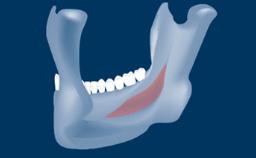

Sinus floor elevation using either the lateral window or transcrestal approach is a predictable surgical procedure with proven success, low complication rates, and high survival rates.

• intraoperative complications of lateral window sinus floor elevation

• intraoperative complications of transcrestal sinus floor elevation